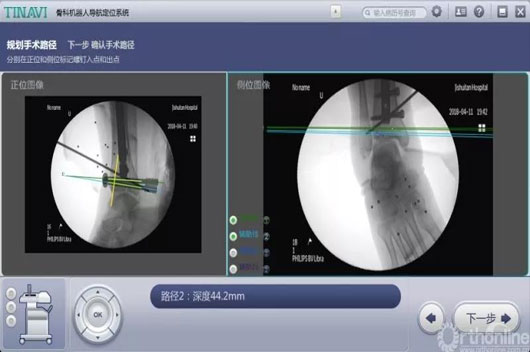

这两台手术划分是机械人辅助后踝骨折闭合复位空心钉牢靠术和机械人辅助距下枢纽融合术。。。。。。。特殊是机械人辅助距下枢纽融合术,,,,,敌手术的精准度要求很是高。。。。。。。

古板手术要领需要大面积袒露患部,,,,,导针重复操作确定位置、同时多次透视,,,,,手术时间长、患者损伤大,,,,,并发症几率高。。。。。。。而现在只需要把融合的枢纽面举行处置惩罚后,,,,,装置好骨科导航机械人,,,,,把伤口用敷料盖好后,,,,,在病人体外用机械人做妄想,,,,,并凭证妄想精准置入螺钉。。。。。。。病人真正的手术时间大大缩短,,,,,袒露的伤口小、辐射少、手术效果抵达最佳。。。。。。。

术中妄想后踝螺钉位置